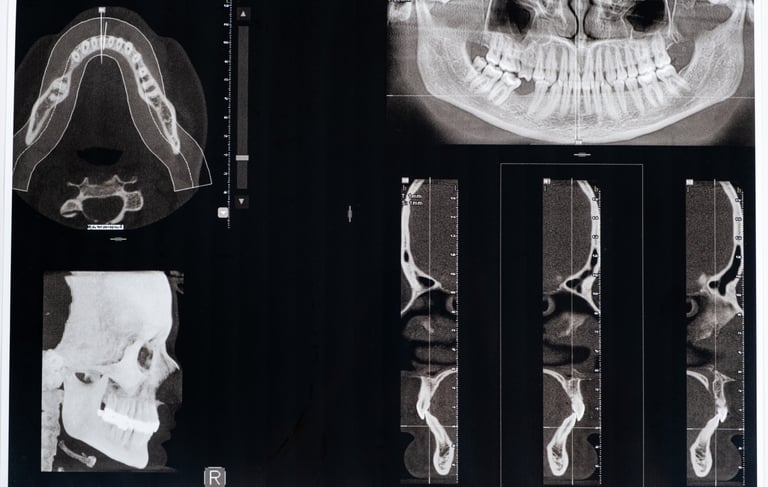

Utiliza imágenes tridimensionales detalladas para evaluar la cantidad y calidad del hueso disponible, así como para planificar la colocación precisa de los implantes.

Tomografía computarizada para planificación de implantes